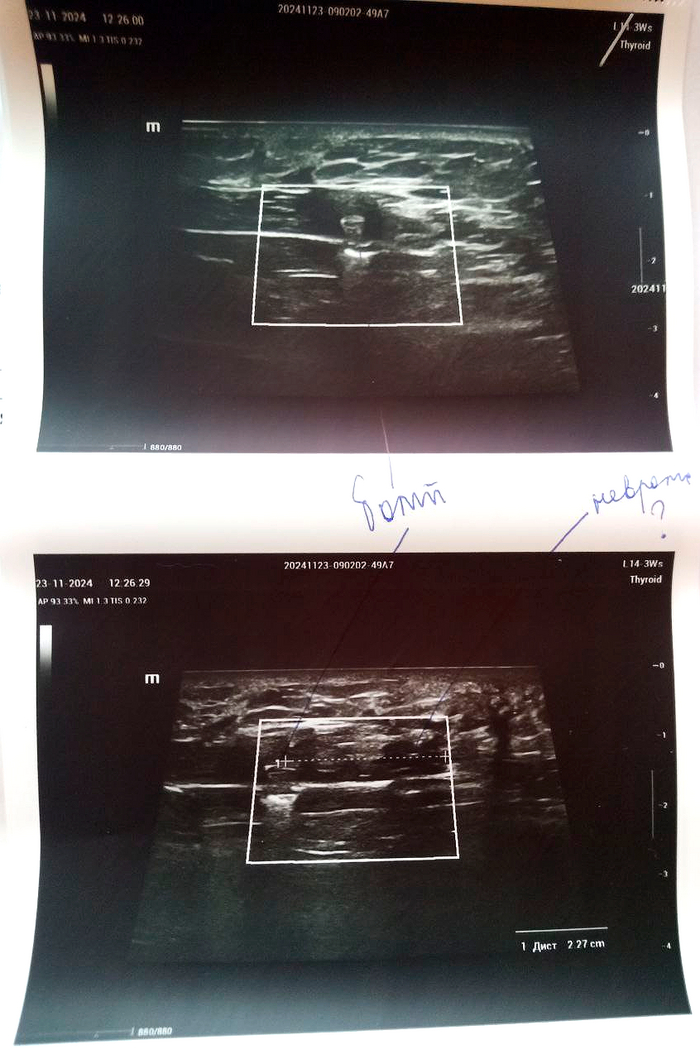

Диагноз невропатолога Комплексный регионарный болевой синдром подтверждён. Руку не отрезаем, нервы не трогаем, посттравматическая нейропатия лучевого нерва под вопросом.